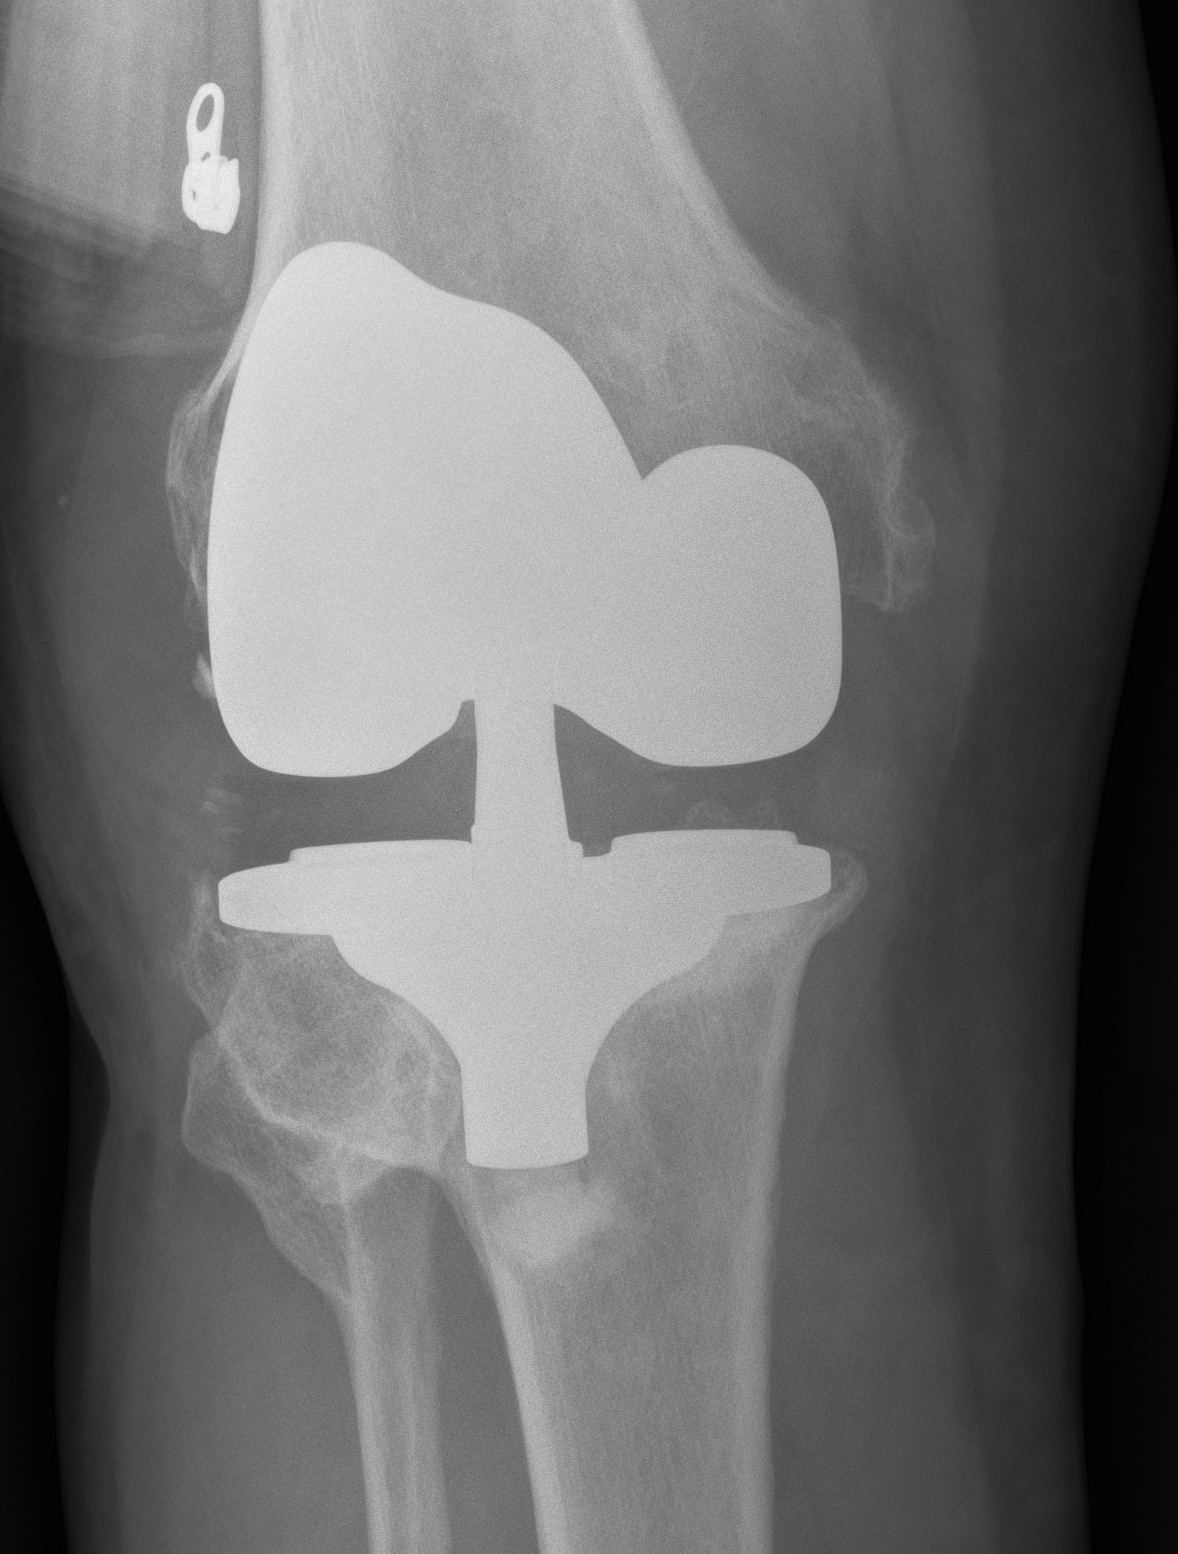

- may need higher constraint